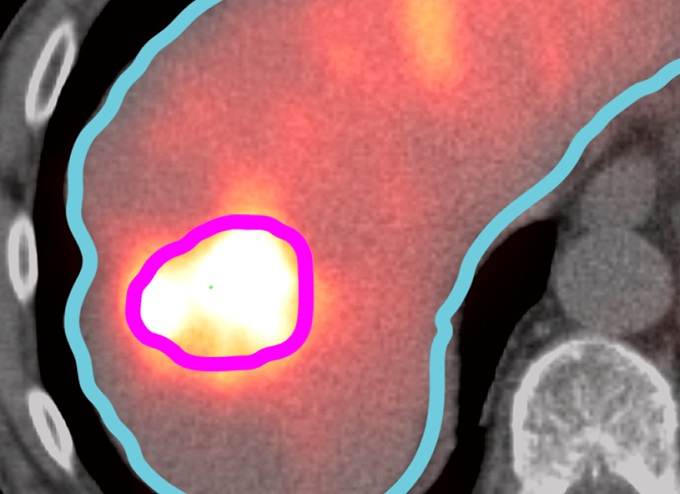

INSYTE with SurePlanTM LiverY90

Our collaboration with MIM Software Inc. means we are able to provide you with SurePlan LiverY90.  This software provides timesaving tools and post-treatment dosimetry for interventional radiologists and nuclear medicine physicians treating hepatic tumors with SIR-Spheres.